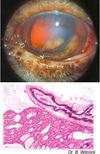

Causes of retinal detachment (separation)

Exudative

– Choroiditis, retinitis – Hemorrhage

– Neoplasm

• Tractional

– maturation of fibrin in vitreous (fibrous adhesions between ciliary bodies = “cyclitic membrane”)

Usually due to inflammation

Retinal detachment due to effusion from the growth of metastatic lymphoma within the choroid and subretinal space

Retinal detachment (separation)

Consequence = retinal degeneration & atrophy

Separates between neural and pigmented layers